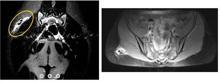

15 ay boyunca ağrısı devam edince genç kız birçok hastaneye gitti ve en sonunda İstanbul Üniversitesi Cerrahpaşa Tıp Fakültesi'ne başvurdu. Burada ameliyat edilen genç kızın kalçasına 10 cm uzunluğunda bir kurşun kalem girdiği ortaya çıktı. Ameliyatı gerçekleştiren İstanbul Üniversitesi Cerrahpaşa Tıp Fakültesi Ortopedi ve Travmatoloji Anabilim Dalı Öğretim Üyesi Prof. Dr. Nuri Aydın, "Meslek hayatımda böyle bir olaya şahit olmamıştım" dedi.

15 ay boyunca kalçasında bir kurşun kalem ile yaşayan genç kızın doktoru Prof. Dr. Aydın, ameliyatı şöyle anlattı: "Hastamızın oturduğunda ağrısı oluyordu. Daha önce birçok doktora gitmiş ve bu ağrının sebebi anlaşılamamıştı. Çok şiddetli ve bazen geceleri bile uyandıran ağrılar yaşamış. Hastayı muayene ettiğimizde kalem olduğuna dair bir bulgu yoktu ancak hasta buzda düştüğünü ve düşme sırasında kalem ucunun batmış olabileceğini bize ifade etti. Röntgende normalde biz metal cisimleri görebiliyoruz ancak bu bir kurşun kalem olduğu için röntgende çok net bir şey görünmüyordu. Hastanın MR'ını çektik ve orada tümör benzeri bir oluşum gördük. Ne olduğu konusunda bizim de bir fikrimiz olmadı o an ve hastayı ameliyata aldık. Ameliyata aldıktan sonra içeriden Yaklaşık 10 cm uzunluğunda bir kurşun kalemin bütün bir şekilde oraya girdiğini gördük. Açıkçası ben de meslek hayatımda ilk kez böyle bir durumla karşılaştım. Hastadan bu cismi çıkardık ve sağlığına kavuştu."